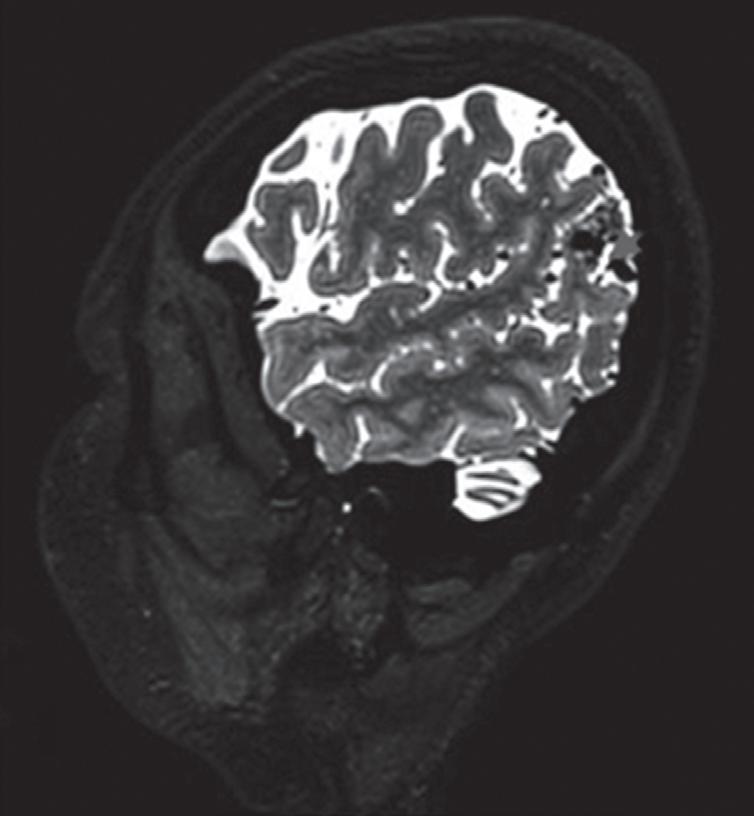

Fig. 1-8. (a-c) RNM T1 com contraste, cortes sagital (a), coronal (b) e axial (c) demonstrando MAV não rota com nidus localizado no lobo occipital à esquerda (setas longas). (d) Arteriografia digital cerebral com injeção de contraste via carótida direita (AP) mostrando a contribuição da carótida direita na irrigação da MAV contralateral. (e,f) Com injeção de contraste via carótida esquerda, em Perfil e AP respectivamente, observa-se nidus compacto nutrido por ramos da artéria cerebral média à esquerda e a veia de drenagem precoce se dirigindo para o seio sagital superior. Projeções em AP (g) e em perfil (h) demonstrando a contribuição do sistema vertebrobasilar por meio de ramos distais da artéria cerebral posterior à esquerda e drenagem para os seios sagital superior e sigmoide à esquerda (setas curtas).

Fig. 1-9. RNM T2 em cortes (a) axial e (b) sagital. (c,d) Tractografia axial – sagital, demonstrando a posição de uma MAV não rota localizada na superfície basal do lobo frontal, nos giros orbitários e reto à direita (setas longas). Arteriografia digital cerebral com injeção de contraste via carótida direita, (e) AP e (f) em perfil demonstrando MAV nutrida por ramos da artéria cerebral média e cerebral anterior direita e drenagem para o seio sagital superior (seta curta).